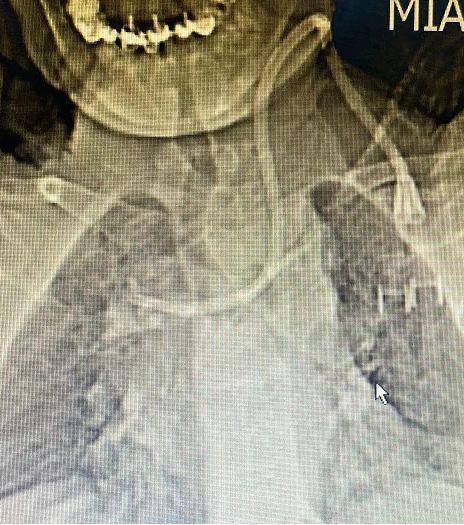

王女士,确诊尿毒症7+年时间,长期依靠左侧cuff导管行血液透析治疗,因确诊导管感染,经过反复治疗后效果不佳,所以必须拔除维持患者生命的唯一的血管通路,但是血管通路是尿毒症患者维持生存的必备条件,目前患者又处于病危状态、高钾、水负荷重,心衰明显,必须立即建立新的血管通路行血液透析治疗去维持生命,由于患者自身血管条件差,动静脉内瘘建立困难,临时血管通路建立难度极大,临时安置股静脉导管、颈内静脉导管均失败,不能满足血液透析要求,对此,患者悲痛欲绝、陷入绝望,家属也不放弃任何能够救治的机会,啃啃哀求郑医生能够为患者开辟一条“活路”;于是肾病科主任毕伟红、副主任王婷立刻紧急召开血管通路小组会议,由于王女士基础疾病多且复杂,DSA下造影显示左侧头臂静脉重度狭窄伴血栓形成,手术难度及风险极大,经过讨论,主刀医生郑星和张艳玲医生快速为患者量身定制手术方案,决定联合运用介入技术(DSA)+PTA技术,为王女士开辟一条新的“活路”。王女士,确诊尿毒症7+年时间,长期依靠左侧cuff导管行血液透析治疗,因确诊导管感染,经过反复治疗后效果不佳,所以必须拔除维持患者生命的唯一的血管通路,但是血管通路是尿毒症患者维持生存的必备条件,目前患者又处于病危状态、高钾、水负荷重,心衰明显,必须立即建立新的血管通路行血液透析治疗去维持生命,由于患者自身血管条件差,动静脉内瘘建立困难,临时血管通路建立难度极大,临时安置股静脉导管、颈内静脉导管均失败,不能满足血液透析要求,对此,患者悲痛欲绝、陷入绝望,家属也不放弃任何能够救治的机会,啃啃哀求郑医生能够为患者开辟一条“活路”;于是肾病科主任毕伟红、副主任王婷立刻紧急召开血管通路小组会议,由于王女士基础疾病多且复杂,DSA下造影显示左侧头臂静脉重度狭窄伴血栓形成,手术难度及风险极大,经过讨论,主刀医生郑星和张艳玲医生快速为患者量身定制手术方案,决定联合运用介入技术(DSA)+PTA技术,为王女士开辟一条新的“活路”。王女士,确诊尿毒症7+年时间,长期依靠左侧cuff导管行血液透析治疗,因确诊导管感染,经过反复治疗后效果不佳,所以必须拔除维持患者生命的唯一的血管通路,但是血管通路是尿毒症患者维持生存的必备条件,目前患者又处于病危状态、高钾、水负荷重,心衰明显,必须立即建立新的血管通路行血液透析治疗去维持生命,由于患者自身血管条件差,动静脉内瘘建立困难,临时血管通路建立难度极大,临时安置股静脉导管、颈内静脉导管均失败,不能满足血液透析要求,对此,患者悲痛欲绝、陷入绝望,家属也不放弃任何能够救治的机会,啃啃哀求郑医生能够为患者开辟一条“活路”;于是肾病科主任毕伟红、副主任王婷立刻紧急召开血管通路小组会议,由于王女士基础疾病多且复杂,DSA下造影显示左侧头臂静脉重度狭窄伴血栓形成,手术难度及风险极大,经过讨论,主刀医生郑星和张艳玲医生快速为患者量身定制手术方案,决定联合运用介入技术(DSA)+PTA技术,为王女士开辟一条新的“活路”。郑星医生表示在:介入技术能够快速发现患者血管通路问题所在,能让“隐形”的血管可视化,精准定位,提高手术操作成功率;由于王女士左侧头臂静脉重度狭窄伴血栓形成,导管通过狭窄部位困难,然而利用PTA技术能够扩张血管重度狭窄部位,让导管顺利通过,两种技术联合运用,极大地降低手术风险,减少了患者的痛苦。生命线的顺利重置,血液透析治疗的顺利开展,让患者及家属顿时喜笑颜开,重燃了患者生存的希望。

(术前) (术前) (术后)

介入技术(DSA):指通过在血管中注入造影剂,使血管显影,根据血管的分布、形态、位置等变化来判断病变的具体部位、范围及程度,并可经导管行介入治疗。